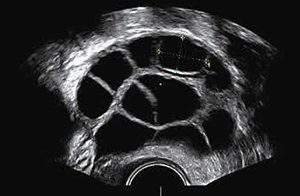

Egg Collection (Oocyte Pick Up)

At the end of the stimulation period, the egg collection can be performed under general anesthesia. This procedure is performed through vagina and under the guidance of ultrasound. A thin needle is introduced into the vagina and into the ovaries, and the follicles that harbor the eggs are aspirated. This fluid is brought to laboratory to pick up the eggs.